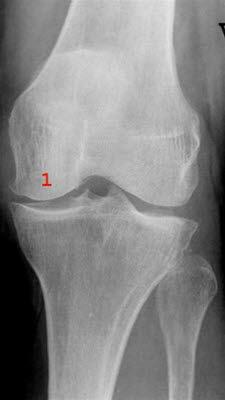

Røntgenbilde av kneleddetKneleddet utgjøres av lårbeinets og leggbeinets leddflater. Beinvevet er kledd med brusk som gjør at leddflatene glir mot hverandre med minst mulig motstand. I tillegg har kneleddet to bruskskiver (meniskene) som fremmer bevegeligheten i leddet. Artrose i kneleddet kalles det når leddbrusk eller bein i kneleddet er endret slik at overflatene ikke lenger er glatte og symmetriske. Dette kaltes tidligere slitasjegikt.

Røntgen av kneet viser typiske artroseforandringer (lette, moderate, uttalte artroseforandringer) og bekrefter diagnosen. Røntgenbildene forteller likevel ikke hele sannheten, fordi det kan være manglende samsvar mellom graden av plager og graden av forandringer på røntgen.